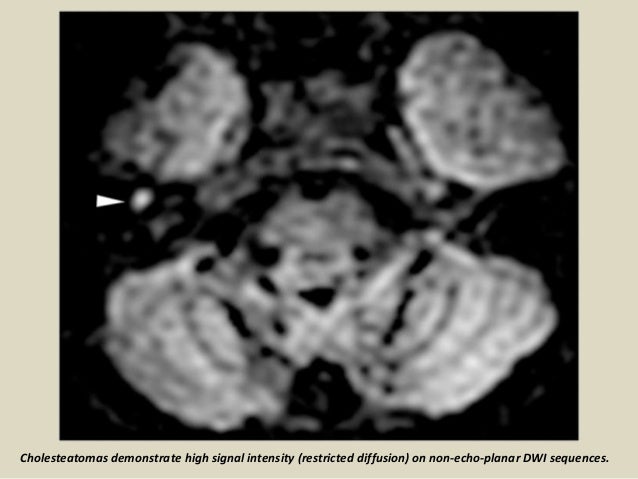

Non echo planar dwi. Compared with the EP DWI sequence, the non-echo-planar diffusion weighted imaging (non-EPI) DW imaging sequence produces thinner slices and has a higher imaging matrix, and it tends to produce fewer magnetic susceptibility artifacts but requires longer imaging times (multi-shot non-echo-planar DWI sequences require approximately 8 min), and non-EPI has higher sensitivity for detecting cholesteatoma and a lower misdiagnosis rate 7, 10, 11, 12. Non‐echo‐planar imaging (EPI) MRI has been recently introduced to improve the detection of small‐sized cholesteatoma and decrease different artefacts occurring in the EPI‐diffusion‐weighted (DW) technique. AIM:To examine the novel use of non-echo-planar diffusion weighted MRI (DWI) in depicting activity and treatment response in active Grave's orbitopathy (GO) by assessing, with inter-observer agreement, for a correlation between its apparent diffusion coefficients (ADCs) and conventional Short tau Inversion Recovery (STIR) MRI signal-intensity ratios (SIRs).

One such non EPI DWI technique is PROPELLER DWI on page (multishot FSE Periodically Rotated Overlapping Parallel Lines with Enhanced Reconstruction), which acquires k-space data in a rotating way, or in blades. On the DWI images with b-value 1000 s/mm 2, a cholesteatoma becomes apparent as a hyperintense area. To examine the novel use of non-echo-planar diffusion weighted MRI (DWI) in depicting activity and treatment response in active Grave’s orbitopathy (GO) by assessing, with inter-observer agreement, for a correlation between its apparent diffusion coefficients (ADCs) and conventional Short tau Inversion Recovery (STIR) MRI signal-intensity ratios (SIRs).

This is important as DWI images the very small motion of water molecules which will be masked by any macroscopic body motion. On the ADC map, a low signal should be visible in the same area, confirming the presence of diffusion restriction. If EPI sequences had a high rate of diffeomorphic atefacts whereas non EPI sequences using either HAlf-Fourier acquisition Single-shot Turbo spin-Echo (HASTE) or Fast.